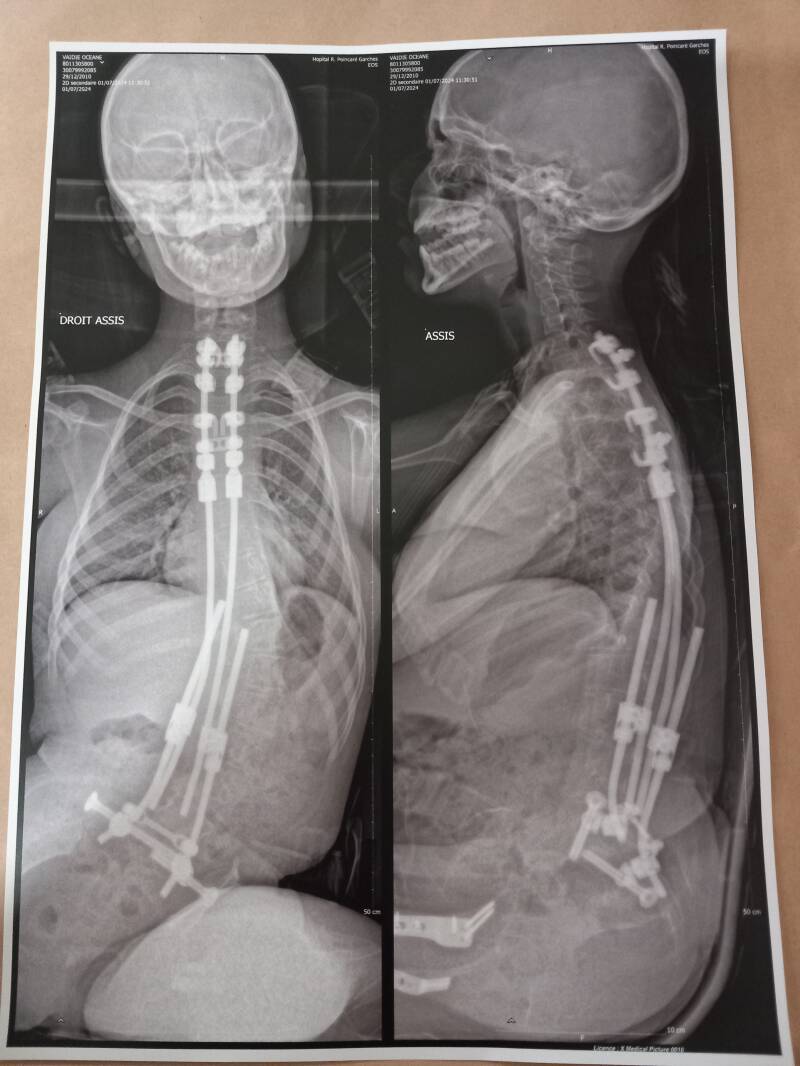

Océane a subi une Arthrodèse vertébrale le 29 février 2024 à l'hôpital Necker à Paris.

Radio d'Océane avant l'opération Radio d'Océane après l'opération

Important : L’arthrodèse vertébrale ne permet pas de stopper la maladie d’Océane.

Elle renforce et maintient seulement la colonne vertébrale.